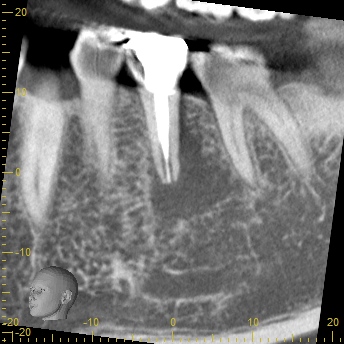

初診時所見: 打診痛(叩いた時の痛み)、根元の圧痛 頬側中央に10mmを超える垂直性歯周ポケットを認めました。

画像診断: レントゲンでは根の周囲に透過像(黒い影)を認め、CTでは根が割れて隙間が空いているようにも見える、非常にVRFの疑いが強い状態でした。